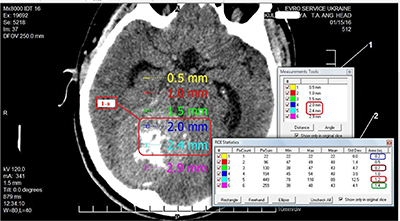

Дані вимірювання розміру пікселів на знімках хворої К. подано на рисунку 1.

Отримані дані програмного визначення розміру пікселя, довжини виділеної ділянки зображення, її площі, а також розрахункового розміру пікселя, довжини та площі зображення внесені до таблиці 1.

Кількість Пікселі (мм) Площа (мм2) розмір (програма) розмір (розрахунок) розмір (програма) розмір (розрахунок) 1 0,5 0,5 0,2 0,25 2 1 1 0,5 0,5 3 1,5 1,5 0,7 0,75 4 2,0 2,0 1,0 1,0 5 2,4 2,5 1,2 1,25 6 2,9 3,0 1,4 1,5

Раніше нами були наведені результати щодо невизначеностей у рівномірності опромінення тканин за рахунок значущої розбіжності значень оптичної щільності суміжних пікселів та вокселів [30]. Аналіз даних вимірювання розміру пікселів та їхніх похідних у пацієнтки К. (рис. 1, табл. 1) показав таке.

Програмою визначено довжину сторони одного пікселя – 0,5 мм. До четвертого пікселя включно розмір відрізка залишався коректним, але між четвертим та п’ятим пікселем відстань мала бути 2,5 мм, тоді як фактично вона дорівнювала 2,4 мм. Виявлено також розбіжності між результатами визначення площі пікселя програмою (зображення 2, рис. 1) та ручним розрахунком. Програма показала площу 0,2 мм2, але з урахуванням розміру сторони пікселя (зображення 1, рис. 1) площа мала б становити 0,25 мм2. Для ділянок з двох та чотирьох пікселів площа, визначена програмою, збігалася з ручними розрахунками. Для ділянки з трьох пікселів відмінність становила 7,1%, з п’яти – 4,2%, з шести – 7,1%. Цілком можливо, що при збільшенні розмірів ділянки похибка виявить системність характеру, але точність планування променевої терапії ґрунтується на характеристиках вокселя, який складається з окремих пікселів, тому будь-які похибки в DICOM-файлах, що вважаються «золотим стандартом» якості медичного зображення, – неприпустимі.

Так, у першому випадку на зрізі пацієнтки К. розмір пікселя становив 0,5 см, однак розмір відрізка з шести пікселів зменшився між четвертим та п’ятим пікселем (2,0 мм-2,4 мм), тобто замість 0,5 мм становив 0,4 мм, після чого знову дорівнював 0,5 мм (2,4 мм-2,9 мм). При аналізі програмного розрахунку площі виявилася певна закономірність. Площа з першого по другий піксель змінилася на 0,3 мм2, з другого по третій – на 0,2 мм2 , з третього по четвертий – знов на 0,3 мм2, з четвертого по п’ятий – на 0,2 мм2, з п’ятого по шостий – знов на 0,2 мм2, порушивши попередню послідовність. Можливо, при збільшенні кількості вимірювань та розрахунків закономірність виявилася би більш чіткою, але на цьому етапі її слід вважати відсутньою, а похибку програми – випадковою [14].